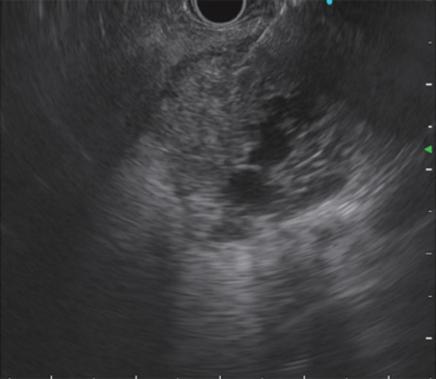

——奥林巴斯高端电子胃肠镜、超声内镜

近期,市中心医院内镜中心引进一套日本奥林巴斯新型EVIS LUCERA ELITE CV290电子胃肠镜系统和EU-ME2 Plus超声内镜诊断仪,作为目前自治区最先进的内镜设备,它拥有革新的技术,为消化系统疾病的诊断和治疗带来巨大变革。

超声内镜(EUS):即内镜和超声相结合的消化道检查技术,将微型高频超声探头安置在内镜顶端,当内镜插入体腔后,在内镜直接观察消化道黏膜病变的同时,可利用内镜下的超声行实时扫描,可以获得胃肠道的层次结构的组织学特征及周围邻近脏器的超声图像,从而进一步提高内镜和超声的诊断水平。

简单来说,医生在使用超声内镜进行检查时,发现病灶,可直接诊断病变的起源层次,并可根据大小、回声特点等初步判定肿瘤性质,是生理性改变还是病理性改变,是器质性改变还是功能性改变等等。

而在之前,患者在做完胃肠镜之后,医生发现病灶,会建议患者至上级医院再做一个超声内镜检查,以便进一步确定病灶的性质,市中心医院超声内镜的使用,直接省去了患者要来回跑去上级医院的麻烦,在内镜中心便可直接进行疾病的诊断及治疗。

随着超声内镜技术在临床的普及,其应用越来越广泛,尤其对于消化道肿瘤的术前分期,明确消化道早癌的浸润深度,合理把握内镜下微创治疗的适应症起到重要作用。有了超声内镜这一有利武器,使得许多疑难复杂的消化系统疾病的诊断和治疗变得容易,从而使市中心医院对消化系统疾病的诊治迈上了一个新台阶。